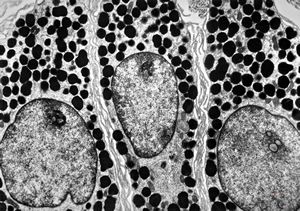

F, 24y. | molluscum contagiosum … virions

F, 24y. | molluscum contagiosum

F, 24y. | molluscum contagiosum

F, 7y. | molluscum contagiosum … virions

F, 7y. | molluscum contagiosum … virions

F, 24y. | molluscum contagiosum … virions